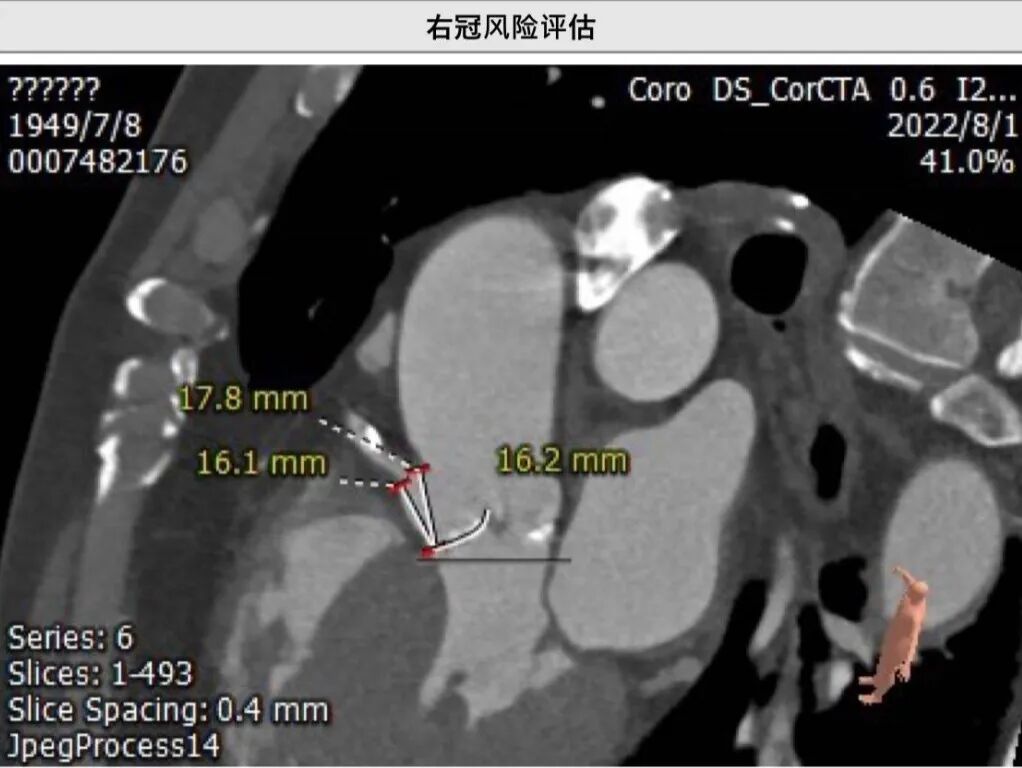

主动脉根部CT测量

瓣环周长:76.8mm

瓣环周长:72.9mm

瓣环角度:50o

左冠高:12.2mm瓣叶长13.1mm

右冠高:16.7mm

瓣叶长: 11.1mm

升主动脉周长:114.3mm

杨毅宁院长总结了该病例特点:

● 患者为高龄女性,主动脉瓣重度狭窄合并轻度关闭不全;

● 右冠开口高度尚可,左冠开口高度较低且瓣叶较长,如选择24瓣膜,冠脉风险低;如选择27瓣膜,存在冠脉风险,建议球扩关注左冠是否需要保护;

● 钙化从瓣环延伸至流出道1.6mm,存在瓣环撕裂风险、传导阻滞风险、瓣周漏风险,建议小球囊预扩。